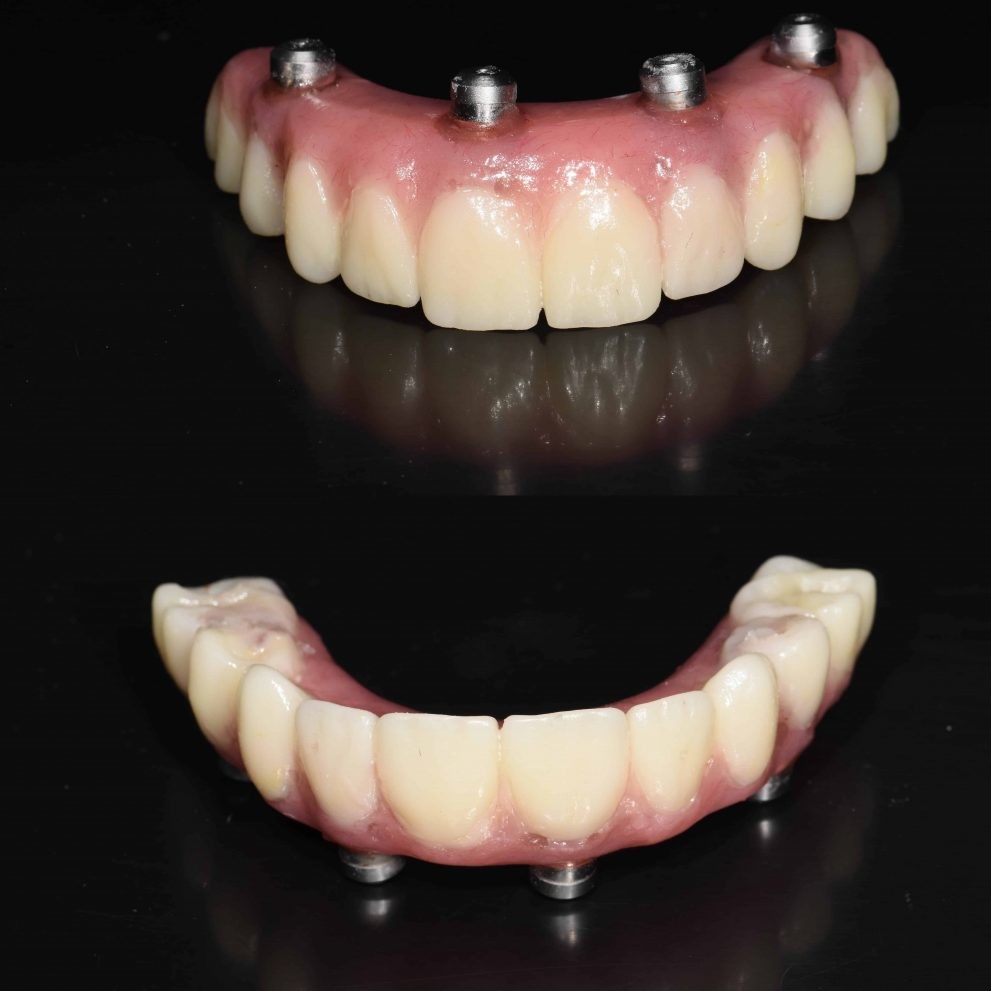

Yes it is possible to get a whole new set of teeth

Struggling with dental issues can be painful and stressful. If you’ve been dealing with tooth loss and wish you could have a new set of teeth, implant surgery can make this happen.

Can I have all my teeth pulled and get implants?

Yes, it is possible to get a whole new set of teeth. This is often the route chosen by those who have been dealing with dental distress for years.

Permanent dental implants are made with metals like titanium or zirconia. They are embedded well into the gum line and act just like the roots of your teeth. Replacement teeth are then affixed onto these implants. Dental implants can last a lifetime and are considered to be a permanent solution for tooth loss. All-on-four and all-on-six dental implant surgeries can be done to give you a new set of teeth in just one jaw or your entire mouthful of teeth.

The experienced dentists at Dental Artistry are able to insert implants in your jaw and fix in a whole new set of teeth that are anchored firmly by the implants. Not only are these a permanent, more efficient solution but they also prevent bone loss or erosion and the consequent sagging of the face often associated with dentures.

How many implants are needed for a full mouth?

Dental Artistry offers the option of giving you a full set of teeth with just four sets of implants. This surgical procedure is called all on four. One implant can hold in place multiple teeth. Sometimes your dentist may recommend that you have six implants instead of six, this is called the all on six procedure. Your dentist will advise how many implants are best for your needs.